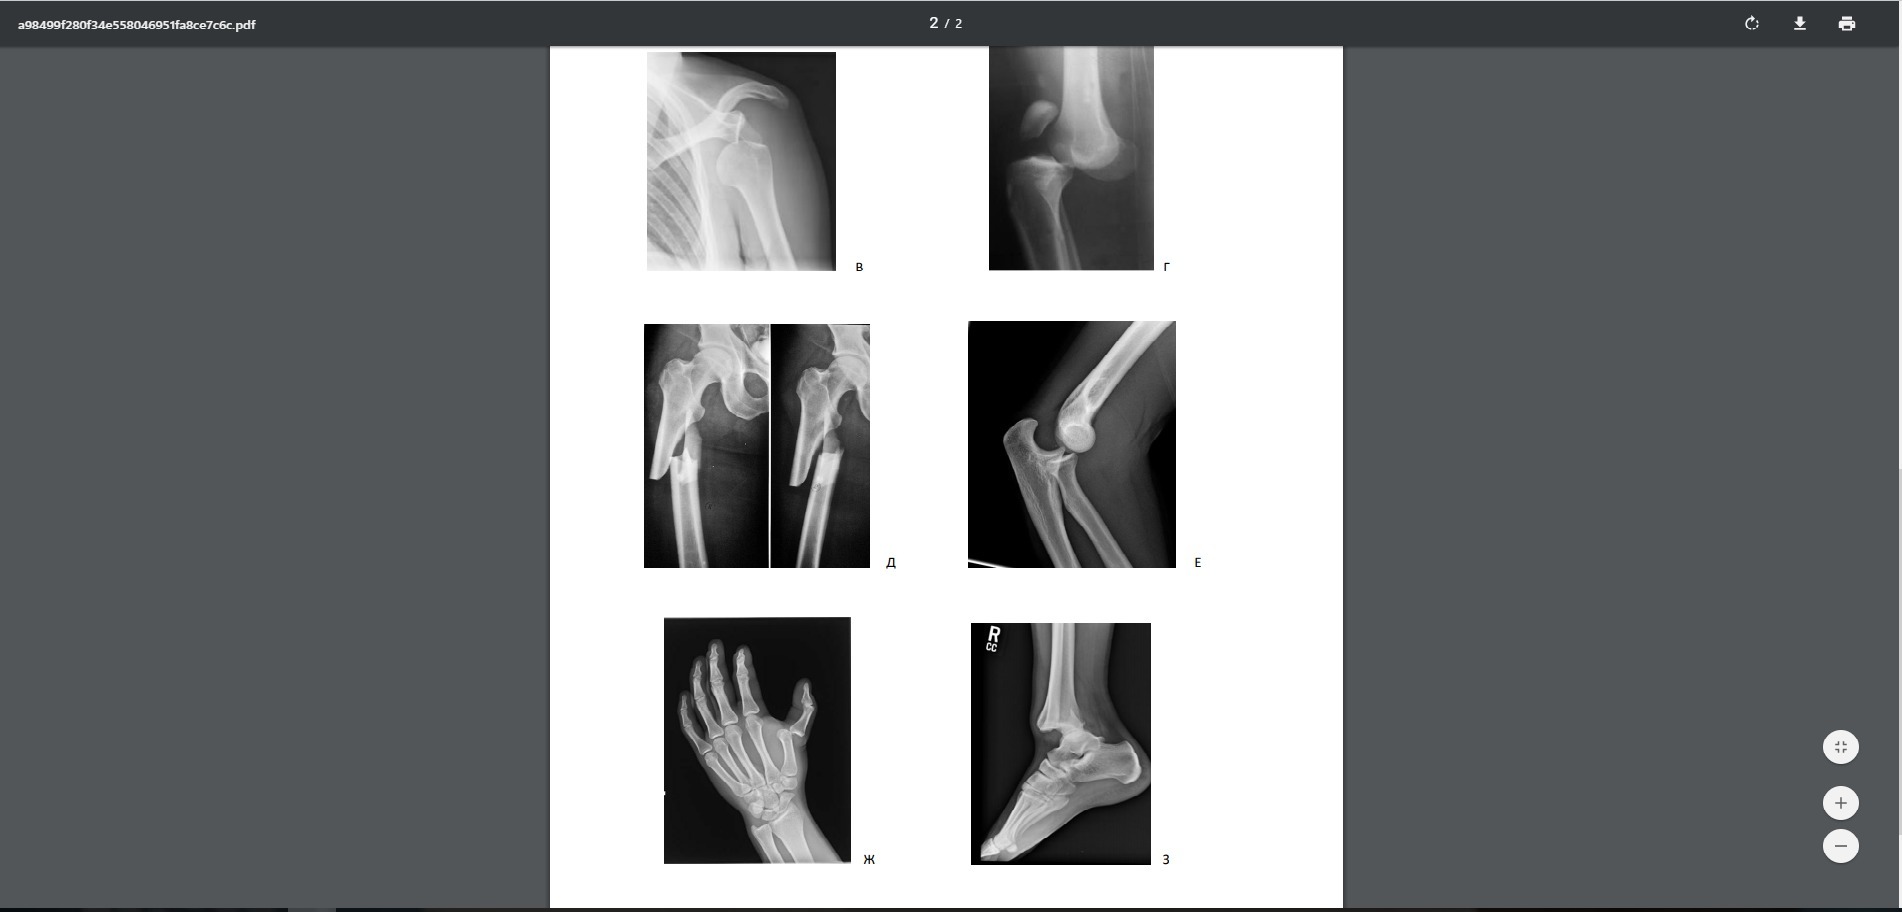

Ответы

первый перелом на колилини 2 перелом возле пятки 3 перелом на плече 4 перелом на колини